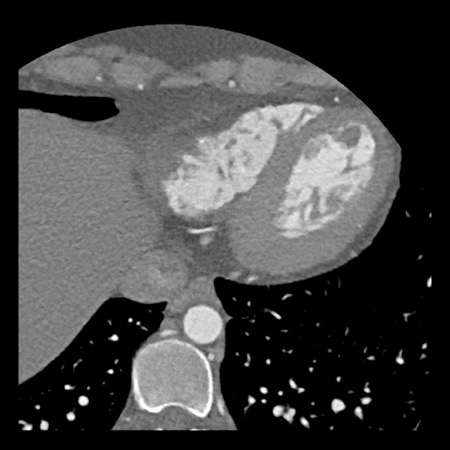

Same patient. First, study the CTA image.

How would you describe the findings?

The coronal image shows a central low-attenuation area around the lumen

of the LAD.

This low-attenuation area is surrounded by a higher attenuation

area.

This finding is the earlier discussed napkin-ring sign, which is a high-risk

plaque feature.

This patient classifies as CAD-RADS 4A/P1/HRP.